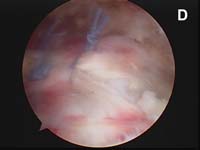

For the most common type of rotator cuff tears, the tendon of the rotator cuff muscle called the supraspinatus will have torn and pulled back slightly from its normal attachment at the greater tuberosity atop the humerus. These smaller tears which are "non-retracted" or "minimally-retracted" only need to be freshened or débrided back to stable, healthy tendon tissue, then mobilized back to the tuberosity and fixed in place. (See Fig. 9) When using an all arthroscopic technique, the surgeon will employ special devices called "suture anchors" to hold the tear in position when it heals. These "anchors" can be made of metal or absorbable compounds. They are screwed or pressed into the bone of the attachment site and the attached sutures are used to tie the edge of the rotator cuff in place.

As tears become larger, they deform and the tendon tissue "shrinks". Thus, larger tears need to be refashioned, repaired side-to-side, or "zipped" closed using a technique called margin convergence. This technique is analogous to zippering shut an open tent flap. The rotator cuff tissue is freed from a scarred, retracted position and repaired side-to-side to ‘close the tent flap’ and restore the tissue over the top of the humeral head. (See Fig.4 and Fig.10) The repaired cuff tissue is then fixed to the site it originally tore away from using specially-designed implants called suture anchors. These are metallic or absorbable plastic devices that secure sutures to the bony attachment. The sutures are then sewn through the torn edge of the cuff to complete the repair.

Absorbable "suture anchors" or implants are gradually absorbed and the sutures attached are incorporated into the healing tissues. When metallic anchors are used (a matter of surgeon preference), these are buried in the bone, and do not affect the integrity of the bone or the shoulder joint. Further surgery is NOT normally required to remove the suture anchors after healing.